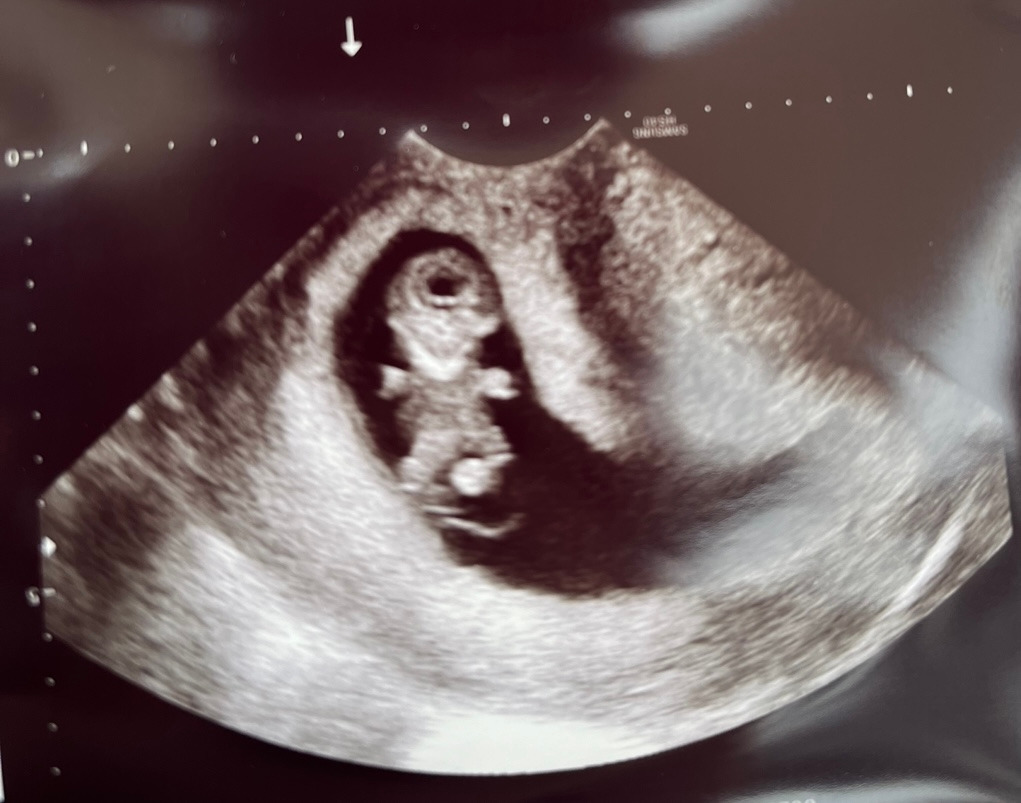

이 글을 쓰는 지금, 어느덧 임신 10주 차에 접어들었다.

병원에 갈 때마다 아주 건강하게 잘 자라고 있다는 이야기를 듣고 매번 안심하고 있다.

계획에 없던 임신인 터라 미리 하지 못한 산전검사를 8주 차에 보건소에서 진행했고, 9주 차에 분만 예정 병원으로 이동해서 나머지 검사를 진행했다.